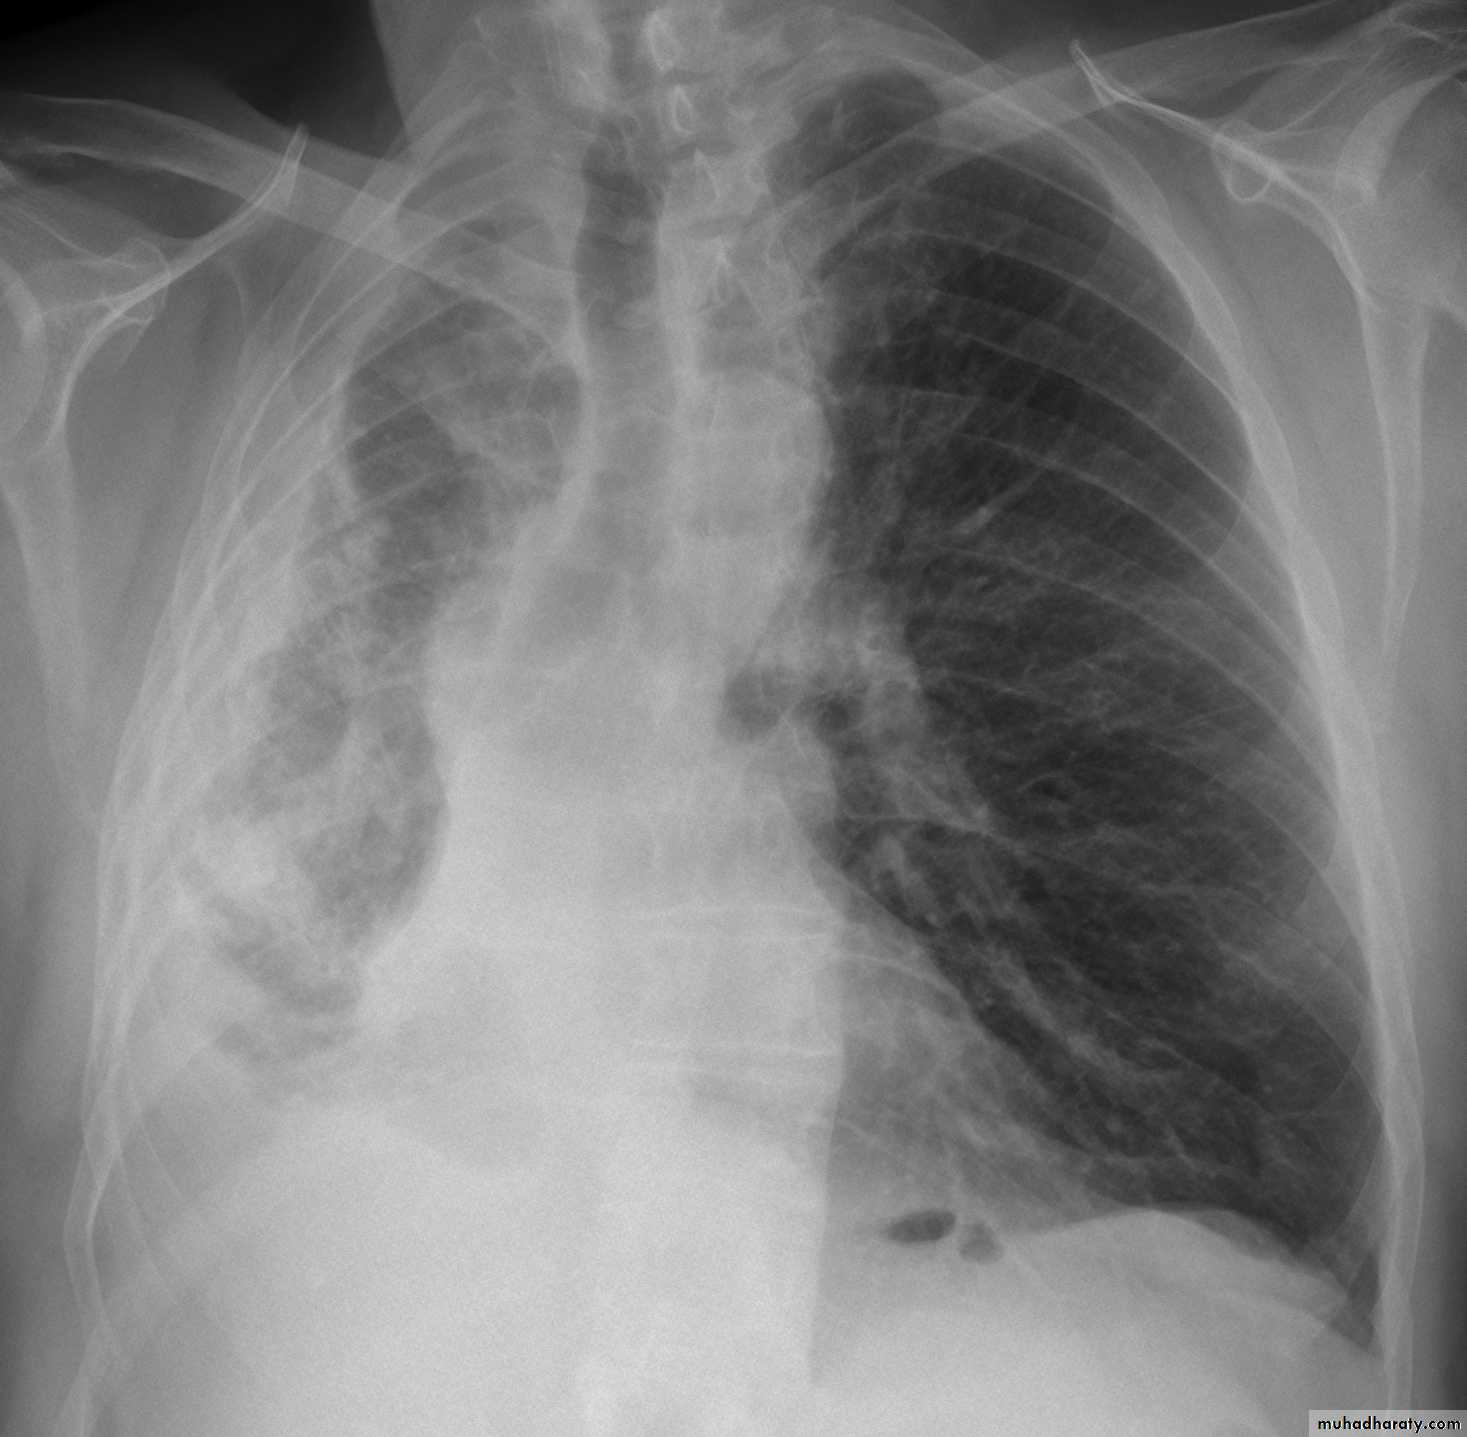

What is the difference??

Massive effusion

Whole lung atelectasisEmpyema

CXR: